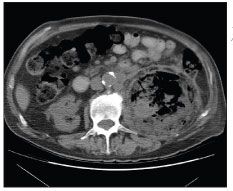

An abdominal radiograph revealed gas surrounding the left kidney (Figure 1), and a CT scan of the abdomen and pelvis showed a large area of gas and fluid in the left renal fossa within the Gerota fascia (Figure 2). Percutaneous drainage of the abscess was performed using a 10 French Cope loop all-purpose drainage catheter. A diagnosis of EPN was made.

Figure 2 –A CT scan of the abdomen shows a large area of gas and fluid in the left renal fossa within the Gerota fascia.